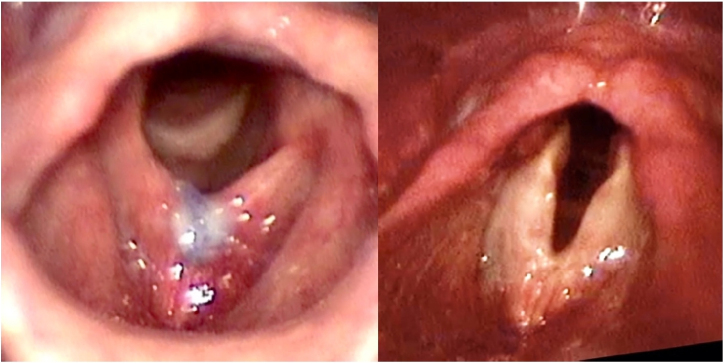

A total of 7 patients were included. The mean age was 35.4 years (range 27–45 years). The mean time of multidisciplinary monitoring at the service before undergoing glottoplasty was 4.1 years (range 2–7 years). The mean number of weekly sessions of preoperative speech therapy was 24.6 (range 13–54 sessions), with a mean period of 5.7 months. Three (43%) patients underwent glottoplasty in isolation, while 4 (57%) underwent glottoplasty with chondrolaryngoplasty to reduce laryngeal prominence, as reported in a previous case series.32 The mean duration of the surgery was 1:10 h. Fig. 2 presents pre- and postoperative laryngoscopy for patient #5.

Figure 2.

Laryngeal image before (left) and 3 months after glottoplasty (right) in inspiration, patient #5.